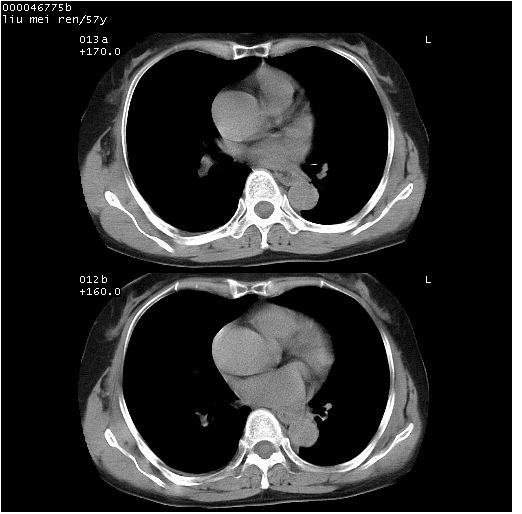

患者 女,57岁。因车祸受伤,其家属要求行“全身ct检查”。平素健康。

胸部ct轴位平扫(层厚10mm,螺距1.5,重建间隔10mm),图像如下:

上腔静脉变异

左位上腔静脉,先天变异。